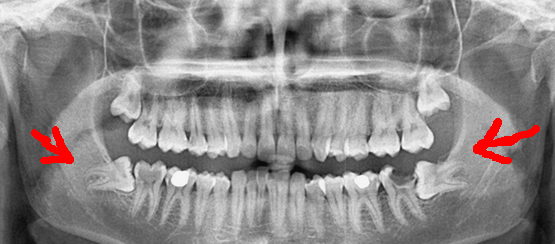

20 yaş dişleri aslında sağlıklı birer diştir. Sağlamdır. Ağrısız ve düzgün çıkan hiç bir 20 yaş dişi kesinlikle çekilmemelidir. Fakat hem beslenme alışkanlıkları nedeniyle hem de zamanla insanların çene yapıları daha dar bir hal aldığı için dişler ağızda yeterli alan bulamamaktadırlar. Bu da 20 yaş dişlerini çözülmesi gereken bir sorun haline getiriyor.

20 yaş dişleri ilk başta şişerek ortaya çıkar. Çenenin arka tarafında ağrı oluşur. Şişkinlik bir süre sonra geçer ama birden tekrar şişkinlik olur. Bu yüzden sıkıntılı ve sancılı bir süreç işler. Eğer beklenirse kesinlikle 20 yaş dişleri zaman içerisinde dışarı doğru çıkar. Bu çıkan diş diğerlerinden ayrı bir şekilde hareket ettiğinden dolayı birçok sıkıntısı bulunmaktadır. Bu yüzden erken tedavisi önemlidir.

Aslında yazımızın içeriğinde buna kısmen cevap verdik. Bunun en önemli sebebi ağızda dişlerin yeteri kadar hareket edememesidir. Kendisine yer bulmak isteyen sağlam dişler, çenede sancılı bir sürecin başlamasına neden olmaktadır. Dayanılmaz hal alan acıların tedavi edilmediğinde daha vahim sonuçlar doğurduğunu söylemek gerek. 20 yaş dişinin kendisini engelleyen kemiği delmek için fizyolojik olarak iltihaplanma başlatacaktır ve başarılı olursa diğer dişlerinize çok ciddi bir baskı uygulayarak yerlerinin değişmesine yani çapraşıklık sorununa sebep olacaktır ki bu da sağlam bir ağrıya sebep olur. Bir diğer önemli sorun ise gömülü 20 yaş dişlerinin zamanla Kist ve Tümör oluşumuna sebebiyet vermesi olasılığıdır.